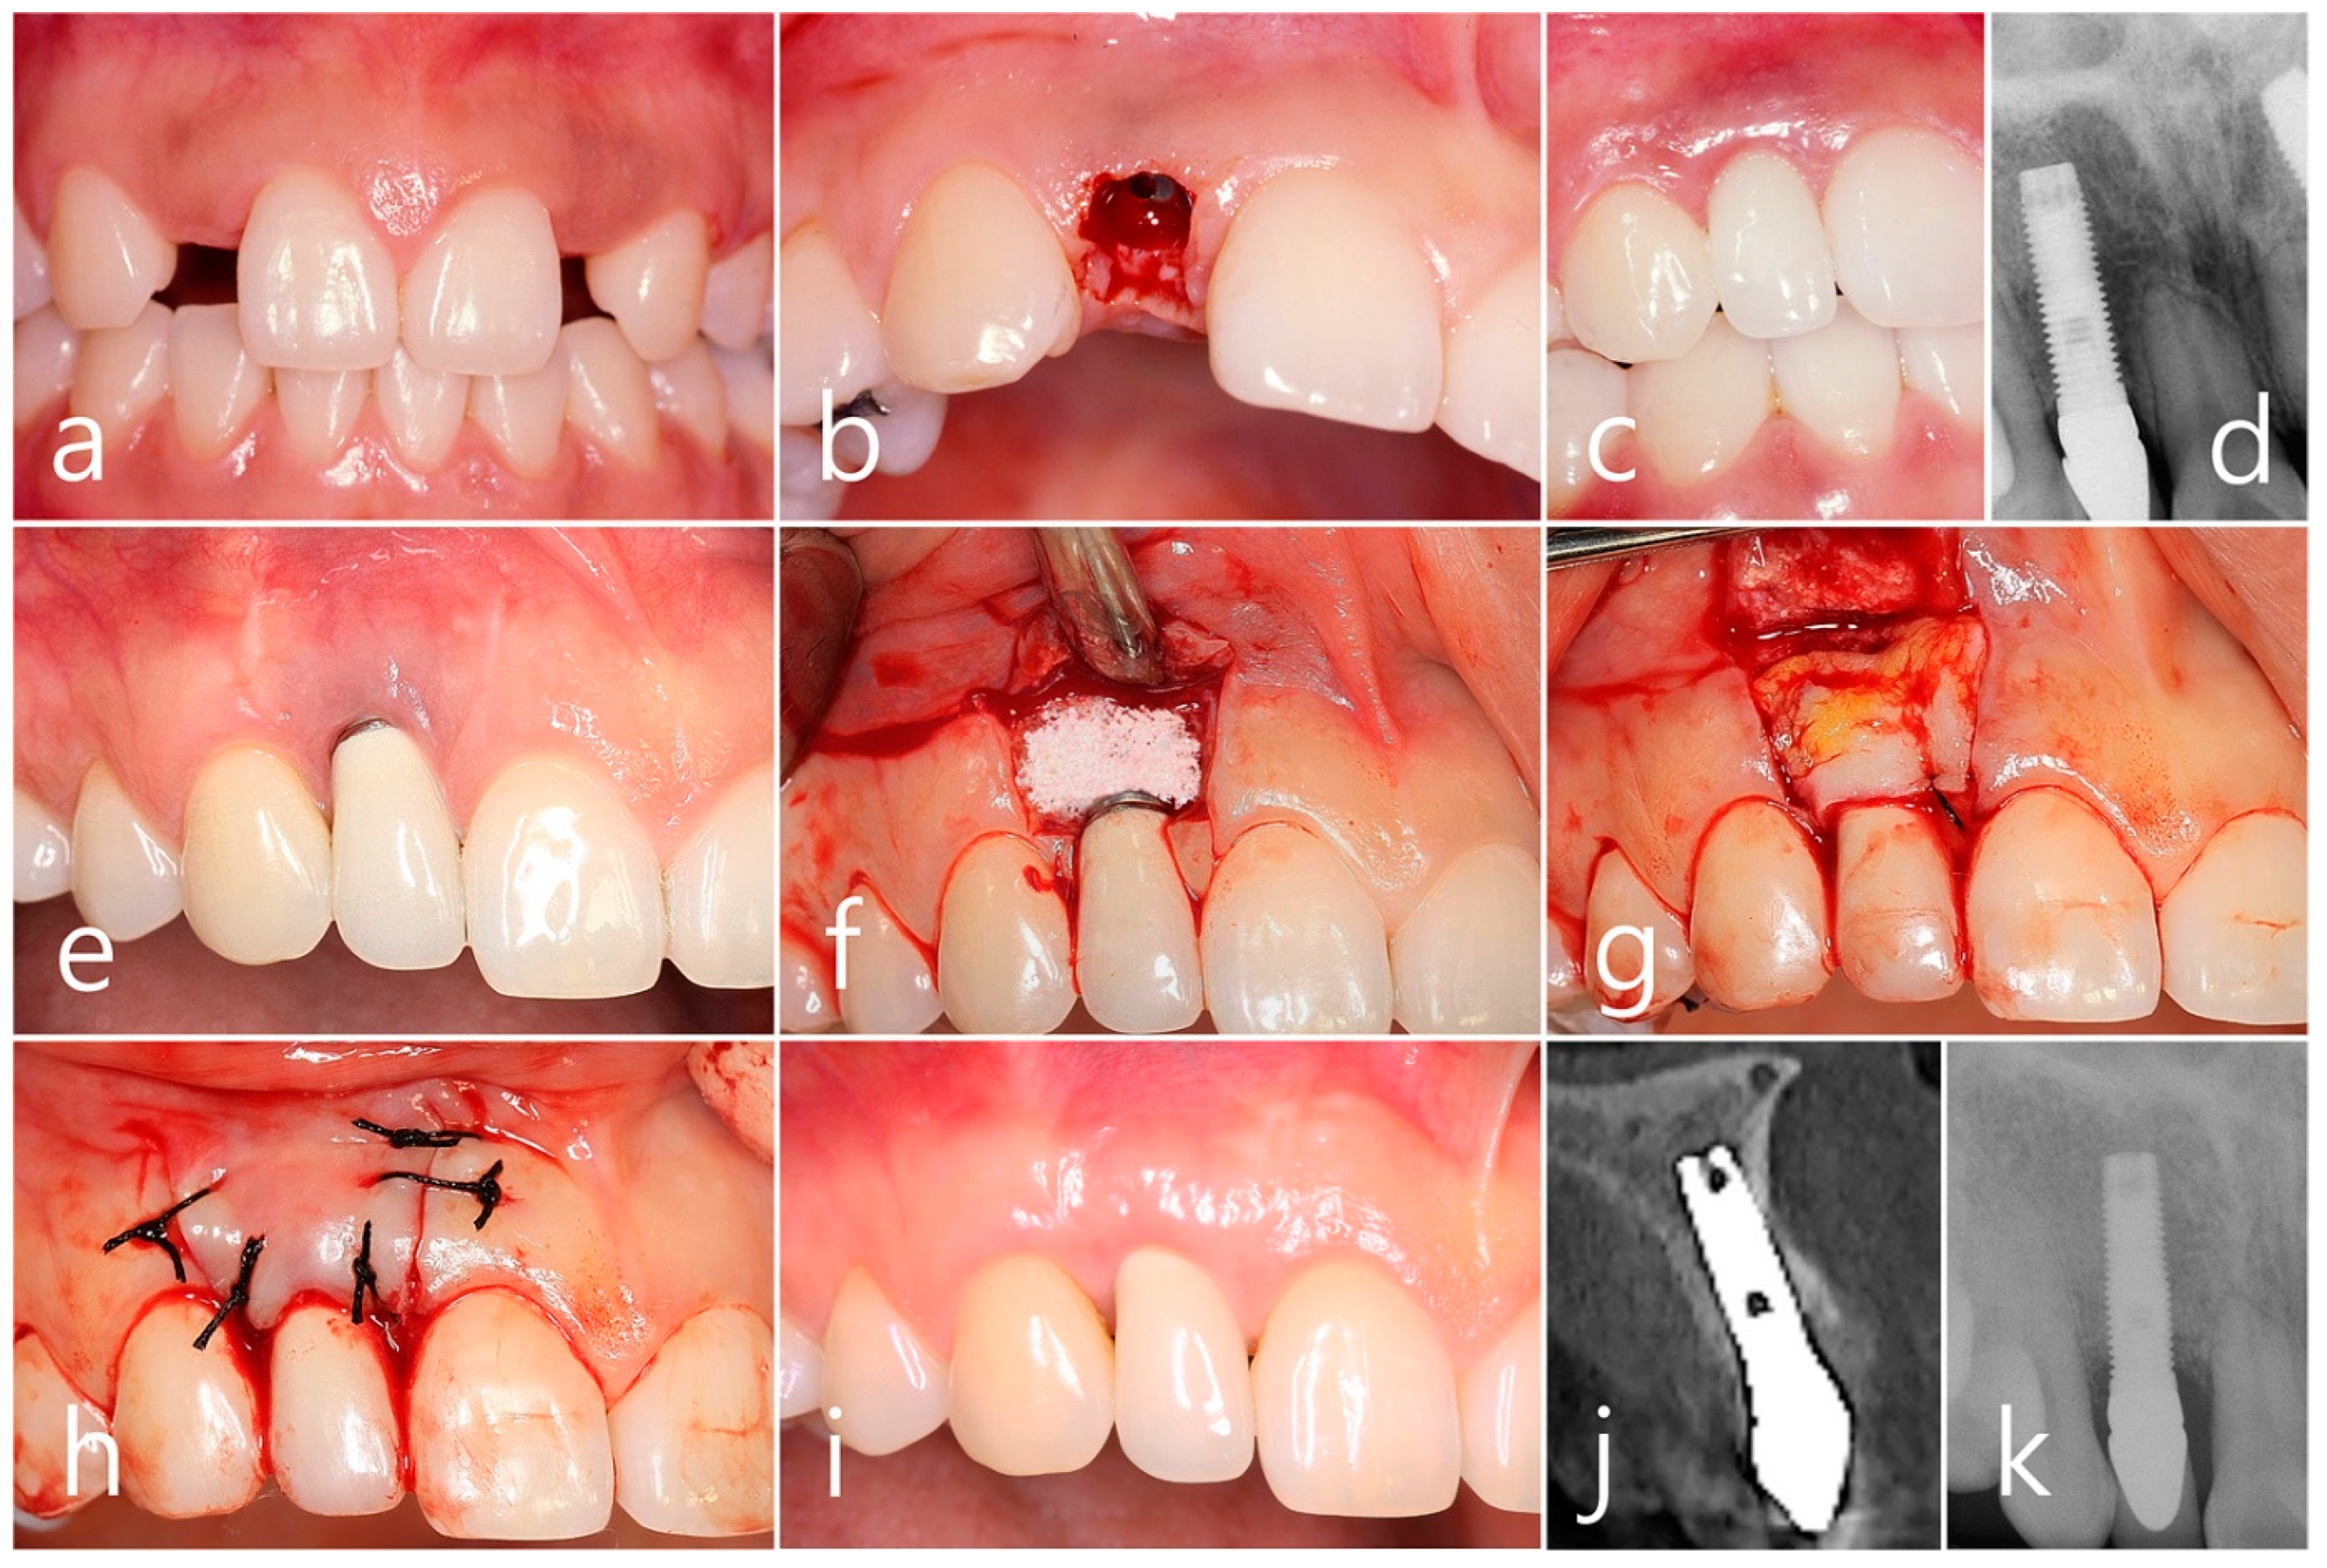

2.3. Case 3